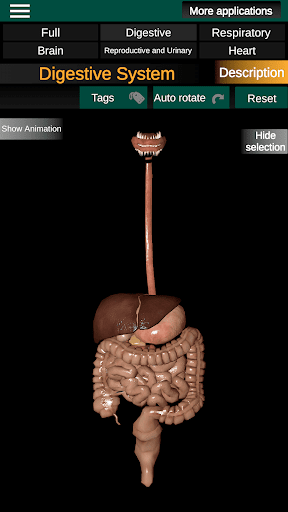

* Травна система, включаючи шлунок, тонку кишку, товсту кишку та анімацію цієї системи.

* Легкий доступ і навігація (масштабування, 3D-обертання).

* Описи кожного органу.